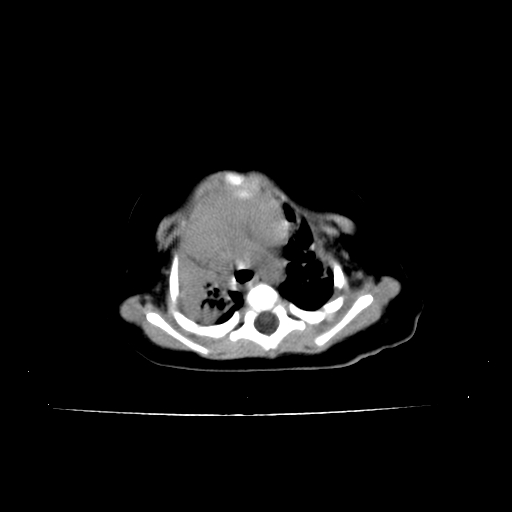

以下是引用影像之路在2009-5-8 15:46:00的发言:[br]1)胸廓畸形。2)考虑两肺感染性病变,并右肺上中叶肺不张;建议抗炎治疗后复查。3)胸腺肥大。4)前上中纵隔占位性病变待排;建议追踪复查。

以下是引用余辉在2009-5-8 8:44:00的发言:[br]鸡胸,胸腺肥大,双肺感染性病变,结合病史支原体肺炎可能性大